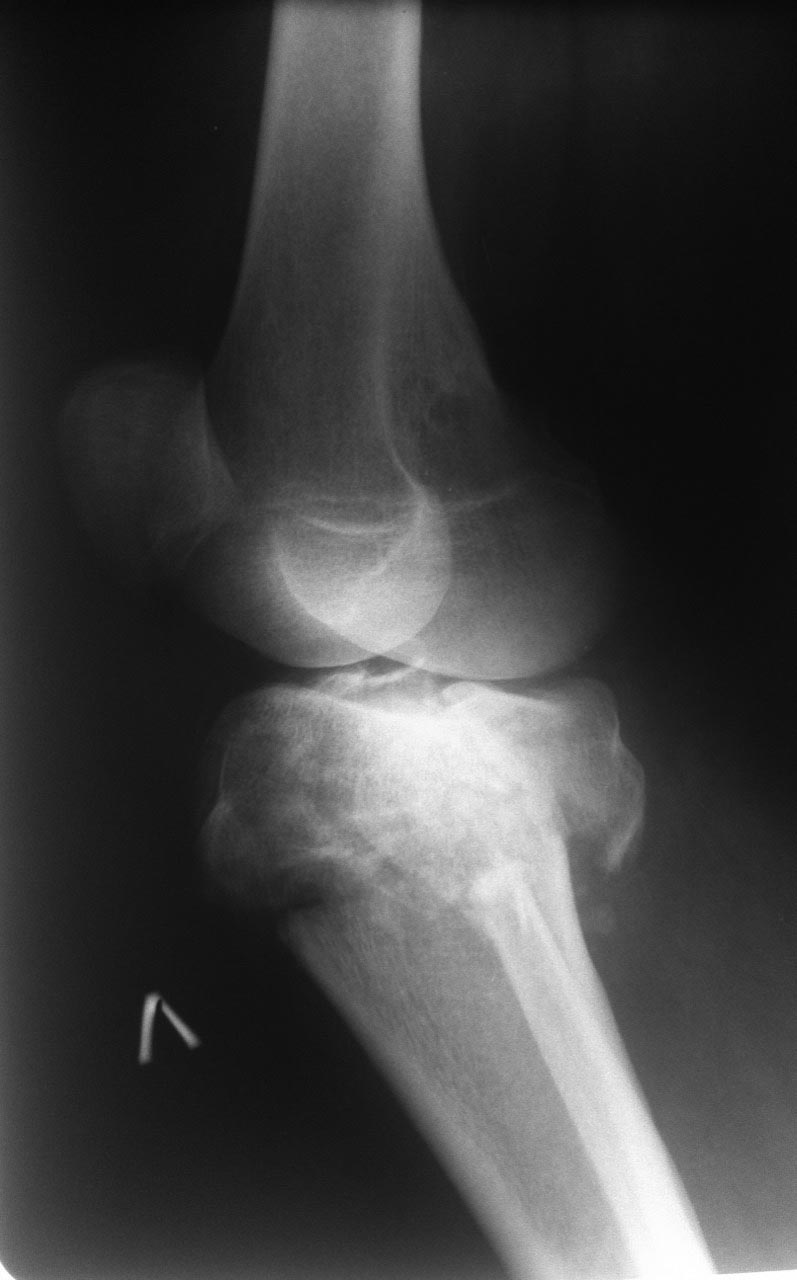

Мужчина 42 года. Травма 5 дней назад, спрыгнул с ж/д платформы (высота порядка 3-4 метров).

Планируется открытая репозиция и остеосинтез 2-мя пластинами. Ну и конечно же пластика костным трансплантатом. Возникла делема, из какого доступа будет лучше работать? А может из 2х? Уже устали спорить и доказывать друг другу свою правоту. Прошу у сообщества помощи..... А какой доступ сделали бы Вы?

Интересная постановка вопроса с Шацкер 6 на 5-е сутки.

Здесь сложный перелом тибиал плато в результате травмы с высокой энергией. На интересующие вопросы ответ можно найти в прежних разборах или на сайте форума, где имеются ссылки на множество книг с описанием современной тактики лечения, включая доступы. Но без прежнего опыта лечения сложных внутрисуставных переломов, такая короткая подсказка не всегда поможет добиться успеха. Кроме этого, одного желания помощь больному не хватает, надо своевременно предоставить запрошенный коллегами материал. Пассивность со стороны автора уменьшает интерес, и обсуждение теряет актуальность! Надеюсь, в этом случае доведем разбор до конца и дождемся результатов операции...

КТ срезы - не ради красоты изображения, а для определения топографии фрагментов! Доступ удобен на верхушке фрагментов, где легко делать репозицию и адекватную фиксацию. С количеством доступов до КТ можно не гадать, только на основании КТ можно определить направление доступа!

Внутрисуставные переломы не терпят долгих бездействии, а решение надо принимать срочно, обычно в день поступления. Стандартные рентген снимки в двух проекциях, и повторить после дистракции. КТ рекомендуется после дистракции! Дистракцию лучше делать наружным фиксатором, но при отсутствии можно на скелетном вытяжении. На вопрос дистрагировать или нет, может ответить характер перелома. При переломах с вовлечением обеих колонн надо делать дистракцию, а перелом одной колонны имеет исключение. Чрезмерный вальгус или варус требуют восстановления оси наружным фиксатором, а небольшие деформации можно оставить на короткое время на шине (knee Immobilizer brace), потому что вторая колонна удерживает от укорочения.